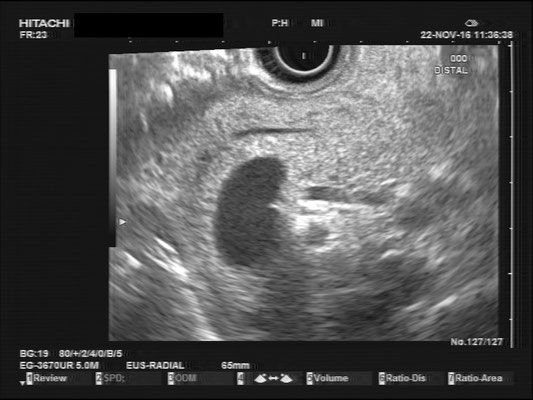

Common bile duct (CBD)

For a full examination of the common bile duct (CBD), we want have a great view of the most distal part, at the duodenal papilla. Optimally we can identify the double duct sign (or as I like to call it the "money shot") and work our way towards the liver. The CBD is joined by the hepatic artery and Portal vein, making up the Glisson's Triad. Using the doppler signal will help differentiate the vessels.

The most observant viewers will have noticed that not all images above depict normal findings but some abnormalities. (my bad ;)